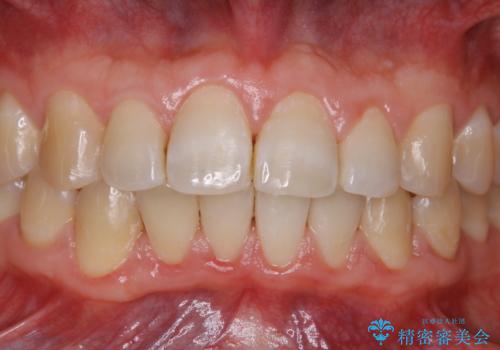

全体的にプラークや歯石が付着していて、歯肉炎が見られました。

状態に合った専門的な器具を使用して、歯質や歯肉へのダメージを抑えながらPMTC(自費クリーニング)60分コースを行いました。矯正治療後の保定装置がワイヤーの場合、フロス・糸ようじが通せないこと、歯ブラシがしずらいことなどにより、歯石プラークなどが付着しやすくなります。そのため専門的な器具による細かいケアを行うことがとても大切です。